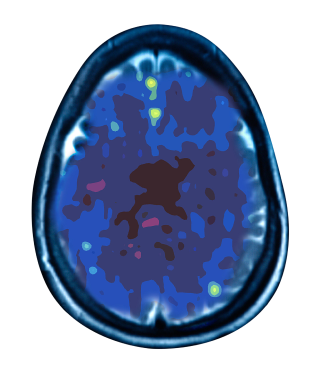

Treating depression at the source

Depressed Brain

Non Depressed Brain